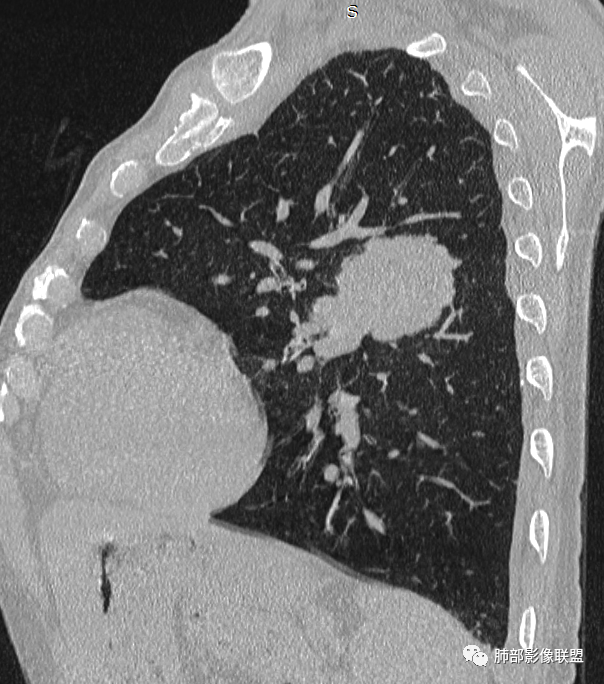

左肺上叶大肿块,膨胀性生长,边界清,密度较低,见部分坏死区,强化弱,肿块见支气管充气V扩张征,分布僵直,枯树枝特点,另一个重要特点血管造影征,淋巴瘤,肿块长轴与胸膜平行,与隐球菌鉴别,隐球荚膜抗原检查,明确诊断经皮肺穿刺。另胸膜钙化(问诊既往有无患胸膜炎病史)。

左肺上叶胸膜下肿块,宽基底与胸膜相连,跨叶裂,边缘清晰膨隆,其内支气管充气,部分扩张、僵直,无明显强化,血管造影征,考虑淋巴瘤,鉴别腺癌

左肺胸膜下巨大占位,跨叶裂,宽基底与胸膜相连,胸膜钙化,平扫密度较低,强化不明显,可见内部血管显影,支气管充气征和扩张,考虑为恶性,倾向于淋巴瘤

大肿块,边缘光滑,深分叶

近端支气管堵塞、推移为主

部分类似于脐凹征

内部支气管扩张

肺动脉推移为主,边缘部分进入

大肿块、表面光滑但深分叶,肺门侧支气管堵塞

回头看,内部支气管近端其实不连续,伴随肺动脉不存在

1)部位:周围型或中央型软组织肿块,以周围型为多见,且肿瘤多位于肺上叶。如本例:该肿瘤位于左肺上叶。

2)大小及形态:由于本病恶性程度高,早期症状不明显,发现时肿块均较大。如本例病变巨大。

3)肿块边界和边缘:多较清楚,呈圆形、类圆形,且由于肿块生长速度不均匀,可见分叶,毛刺少见。有报道肿块周围毛玻璃影是多形性癌特征表现。

4)密度:肿块平扫为软组织密度,由于体积较大,内部常见大片状坏死,可出现不规则厚壁空洞或坏死内多发无壁小空洞,坏死多不均匀:坏死灶内可见如柳絮样的斑片样强化灶,坏死边缘与非坏死区分界不清本例坏死较明显,密度不均匀。